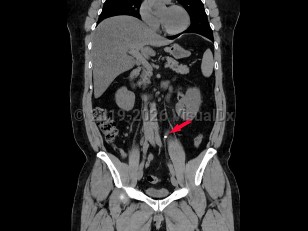

Abdominal aortic aneurysmAbdominal aortic aneurysm

Intraabdominal abscessIntraabdominal abscess